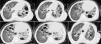

Laboratory findings included: Hb: 11.0g/dL, WBC count: 15.0×109/L with 10% eosinophils and 52% neutrophils, erythrocyte sedimentation rate: 80mm/h, alkaline phosphatase: 211U/L [reference range (RR): 35–150U/L]. No other metabolic abnormalities were observed. Alfa‐1 antitrypsin, serum IgA and IgM levels were within normal limits. IgG: 17.0g/L (RR: 6.4–13.5g/L) and IgE: 21,300U/mL (RR: 10–179U/ml) were high. A chest radiograph performed on admission showed multiple thin‐walled cysts with air‐fluid level consistent with superinfection (Fig. 1). The thorax CT scan alterations are showed in Fig. 2.